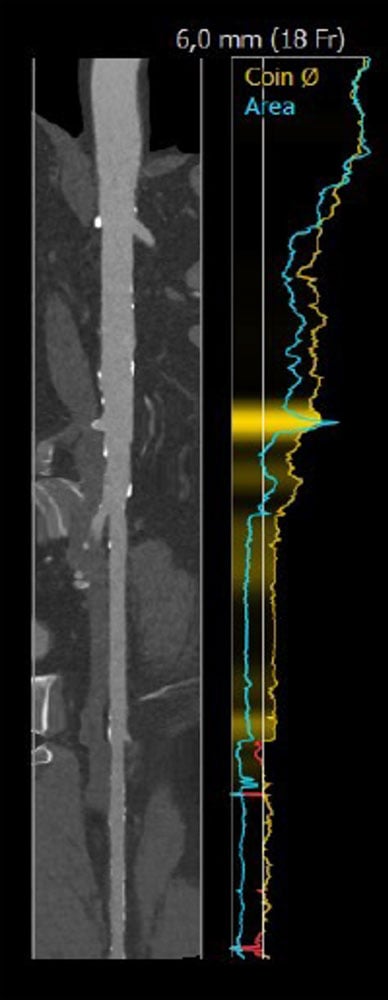

Case planning: CT

Annulus: 29.6 cm

LVOT: 32.2 cm

Moderate Ca2+, tricuspid